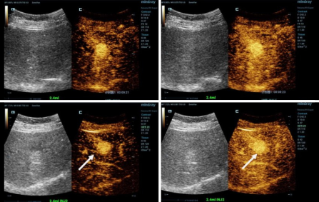

![–Ґ–Њ—З–љ–∞—П –і–Є–∞–≥–љ–Њ—Б—В–Є–Ї–∞ —Б –Ї–Њ–љ—В—А–∞—Б—В–љ—Л–Љ —Г—Б–Є–ї–µ–љ–Є–µ–Љ –Є –≤—Л—Б–Њ–Ї–Њ–є —З–∞—Б—В–Њ—В–Њ–є –Ї–∞–і—А–Њ–≤]() –Ґ–Њ—З–љ–∞—П –і–Є–∞–≥–љ–Њ—Б—В–Є–Ї–∞ —Б –Ї–Њ–љ—В—А–∞—Б—В–љ—Л–Љ —Г—Б–Є–ї–µ–љ–Є–µ–Љ –Є –≤—Л—Б–Њ–Ї–Њ–є —З–∞—Б—В–Њ—В–Њ–є –Ї–∞–і—А–Њ–≤–£–ї—М—В—А–∞–Ј–≤—Г–Ї–Њ–≤–∞—П –і–Є–∞–≥–љ–Њ—Б—В–Є–Ї–∞ —Б –Ї–Њ–љ—В—А–∞—Б—В–љ—Л–Љ —Г—Б–Є–ї–µ–љ–Є–µ–Љ (CEUS) —П–≤–ї—П–µ—В—Б—П –Ї—А–∞–є–љ–µ –і–Є–љ–∞–Љ–Є—З–љ–Њ–є –Њ–±–ї–∞—Б—В—М—О –і–Є–∞–≥–љ–Њ—Б—В–Є–Ї–Є, –Є –Ј–∞ –њ–Њ—Б–ї–µ–і–љ–Є–µ –љ–µ—Б–Ї–Њ–ї—М–Ї–Њ –ї–µ—В —В–µ—Е–љ–Њ–ї–Њ–≥–Є—З–µ—Б–Ї–Є–µ –Є–љ–љ–Њ–≤–∞—Ж–Є–Є –µ—Й–µ –±–Њ–ї—М—И–µ –њ–Њ–≤—Л—Б–Є–ї–Є –Ї–∞—З–µ—Б—В–≤–Њ –Є–Ј–Њ–±—А–∞–ґ–µ–љ–Є–є. –Ю–і–љ–Њ–є –Є–Ј —В–∞–Ї–Є—Е –Є–љ–љ–Њ–≤–∞—Ж–Є–є —П–≤–ї—П–µ—В—Б—П —Г–ї—М—В—А–∞–Ј–≤—Г–Ї–Њ–≤–∞—П –і–Є–∞–≥–љ–Њ—Б—В–Є–Ї–∞ —Б –≤—Л—Б–Њ–Ї–Њ–є —З–∞—Б—В–Њ—В–Њ–є –Ї–∞–і—А–Њ–≤ –Є –Ї–Њ–љ—В—А–∞—Б—В–љ—Л–Љ —Г—Б–Є–ї–µ–љ–Є–µ–Љ (HiFR CEUS), –њ—А–Є –Ї–Њ—В–Њ—А–Њ–є –Љ–Њ–ґ–љ–Њ –њ–Њ–ї—Г—З–∞—В—М –≤ –і–µ—Б—П—В—М —А–∞–Ј –±–Њ–ї—М—И–µ –Є–Ј–Њ–±—А–∞–ґ–µ–љ–Є–є, —З–µ–Љ –њ—А–Є –Њ–±—Л—З–љ–Њ–Љ —Г–ї—М—В—А–∞–Ј–≤—Г–Ї–Њ–≤–Њ–Љ –Є—Б—Б–ї–µ–і–Њ–≤–∞–љ–Є–Є, –Ј–∞ —В–Њ –ґ–µ –≤—А–µ–Љ—П.–£–ї—М—В—А–∞–Ј–≤—Г–Ї–Њ–≤–∞—П –і–Є–∞–≥–љ–Њ—Б—В–Є–Ї–∞ | –Ю–±—Й–∞—П –≤–Є–Ј—Г–∞–ї–Є–Ј–∞—Ж–Є—П 2022-12-16

–Ґ–Њ—З–љ–∞—П –і–Є–∞–≥–љ–Њ—Б—В–Є–Ї–∞ —Б –Ї–Њ–љ—В—А–∞—Б—В–љ—Л–Љ —Г—Б–Є–ї–µ–љ–Є–µ–Љ –Є –≤—Л—Б–Њ–Ї–Њ–є —З–∞—Б—В–Њ—В–Њ–є –Ї–∞–і—А–Њ–≤–£–ї—М—В—А–∞–Ј–≤—Г–Ї–Њ–≤–∞—П –і–Є–∞–≥–љ–Њ—Б—В–Є–Ї–∞ —Б –Ї–Њ–љ—В—А–∞—Б—В–љ—Л–Љ —Г—Б–Є–ї–µ–љ–Є–µ–Љ (CEUS) —П–≤–ї—П–µ—В—Б—П –Ї—А–∞–є–љ–µ –і–Є–љ–∞–Љ–Є—З–љ–Њ–є –Њ–±–ї–∞—Б—В—М—О –і–Є–∞–≥–љ–Њ—Б—В–Є–Ї–Є, –Є –Ј–∞ –њ–Њ—Б–ї–µ–і–љ–Є–µ –љ–µ—Б–Ї–Њ–ї—М–Ї–Њ –ї–µ—В —В–µ—Е–љ–Њ–ї–Њ–≥–Є—З–µ—Б–Ї–Є–µ –Є–љ–љ–Њ–≤–∞—Ж–Є–Є –µ—Й–µ –±–Њ–ї—М—И–µ –њ–Њ–≤—Л—Б–Є–ї–Є –Ї–∞—З–µ—Б—В–≤–Њ –Є–Ј–Њ–±—А–∞–ґ–µ–љ–Є–є. –Ю–і–љ–Њ–є –Є–Ј —В–∞–Ї–Є—Е –Є–љ–љ–Њ–≤–∞—Ж–Є–є —П–≤–ї—П–µ—В—Б—П —Г–ї—М—В—А–∞–Ј–≤—Г–Ї–Њ–≤–∞—П –і–Є–∞–≥–љ–Њ—Б—В–Є–Ї–∞ —Б –≤—Л—Б–Њ–Ї–Њ–є —З–∞—Б—В–Њ—В–Њ–є –Ї–∞–і—А–Њ–≤ –Є –Ї–Њ–љ—В—А–∞—Б—В–љ—Л–Љ —Г—Б–Є–ї–µ–љ–Є–µ–Љ (HiFR CEUS), –њ—А–Є –Ї–Њ—В–Њ—А–Њ–є –Љ–Њ–ґ–љ–Њ –њ–Њ–ї—Г—З–∞—В—М –≤ –і–µ—Б—П—В—М —А–∞–Ј –±–Њ–ї—М—И–µ –Є–Ј–Њ–±—А–∞–ґ–µ–љ–Є–є, —З–µ–Љ –њ—А–Є –Њ–±—Л—З–љ–Њ–Љ —Г–ї—М—В—А–∞–Ј–≤—Г–Ї–Њ–≤–Њ–Љ –Є—Б—Б–ї–µ–і–Њ–≤–∞–љ–Є–Є, –Ј–∞ —В–Њ –ґ–µ –≤—А–µ–Љ—П.–£–ї—М—В—А–∞–Ј–≤—Г–Ї–Њ–≤–∞—П –і–Є–∞–≥–љ–Њ—Б—В–Є–Ї–∞ | –Ю–±—Й–∞—П –≤–Є–Ј—Г–∞–ї–Є–Ј–∞—Ж–Є—П 2022-12-16 -